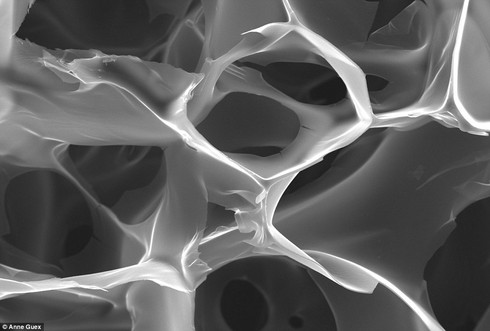

![]() |

Một tác phẩm đáng chú ý khác có tên là “Chồng chất”, được chụp bởi tiến sĩ Anne Geraldine Guex. Nghiên cứu của bà là sử dụng khuôn có những lỗ siêu nhỏ để nuôi các tế bào tim khỏe mạnh, từ đó có thể cấy vào tim của các bệnh nhân khi lên cơn đau. |